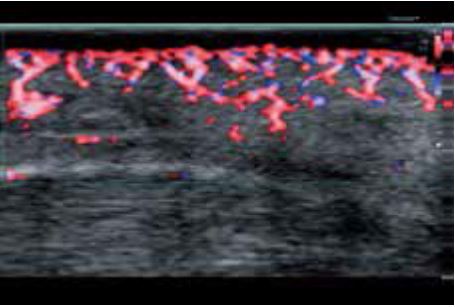

Бешихове запалення

Роздільна здатність зображення, яку забезпечує PLI-2004BX, чітко демонструє підшкірний набряк у місці ураження (рис. 6а). На кольорових зображеннях SMI (cSMI), отриманих за допомогою звичайного лінійного датчика, важко візуалізувати деталі ураження та гіперемію в епідермісі та дермі (рис. 6б). Тоді як вища чутливість cSMI надвисокочастотного датчика легко ідентифікує посилення кровотоку внаслідок сильного запалення (рис. 6в). Крім того, 3D cSMI-зображення, отримане за допомогою PLI-2004BX зі Smart Sensor 3D, одразу відображає всю судинну систему (рис. 6г). Ультрависокочастотний датчик має великий потенціал в дерматології і, як очікується, в повній мірі продемонструє свої видатні можливості з розмежування найдрібніших структур.

а) Сірошкальне зображення

б) cSMI з використанням PLT-1005BT

в) cSMI з використанням PLI-2004BX

г) cSMI зі Smart Sensor 3D з використанням PLI-2004BX

Малюнок 6. Бешихове запалення, виявлене за допомогою PLI-2004BX (24 МГц) ( а, в, г) та PLT-1005BT (12 МГц) (б).